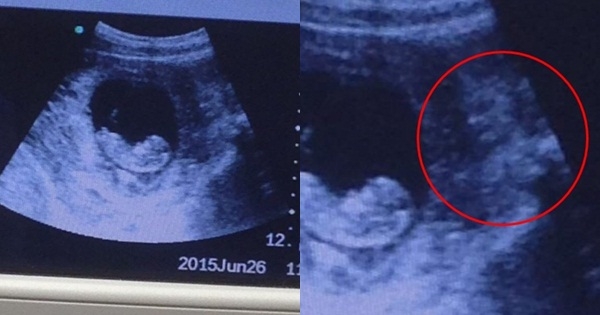

ขนลุกซู่ เงาปีศาจโผล่ภาพถ่ายอัลตราซาวด์ จ้องทารกเขม็ง